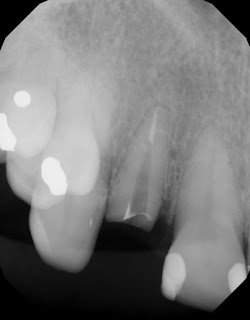

The endodontists at Superstition Springs Endodontics are skilled in restorative procedures closely associated with endodontic treatment. At your request, esthetic post and core buildups can be immediately placed following endodontic treatment.